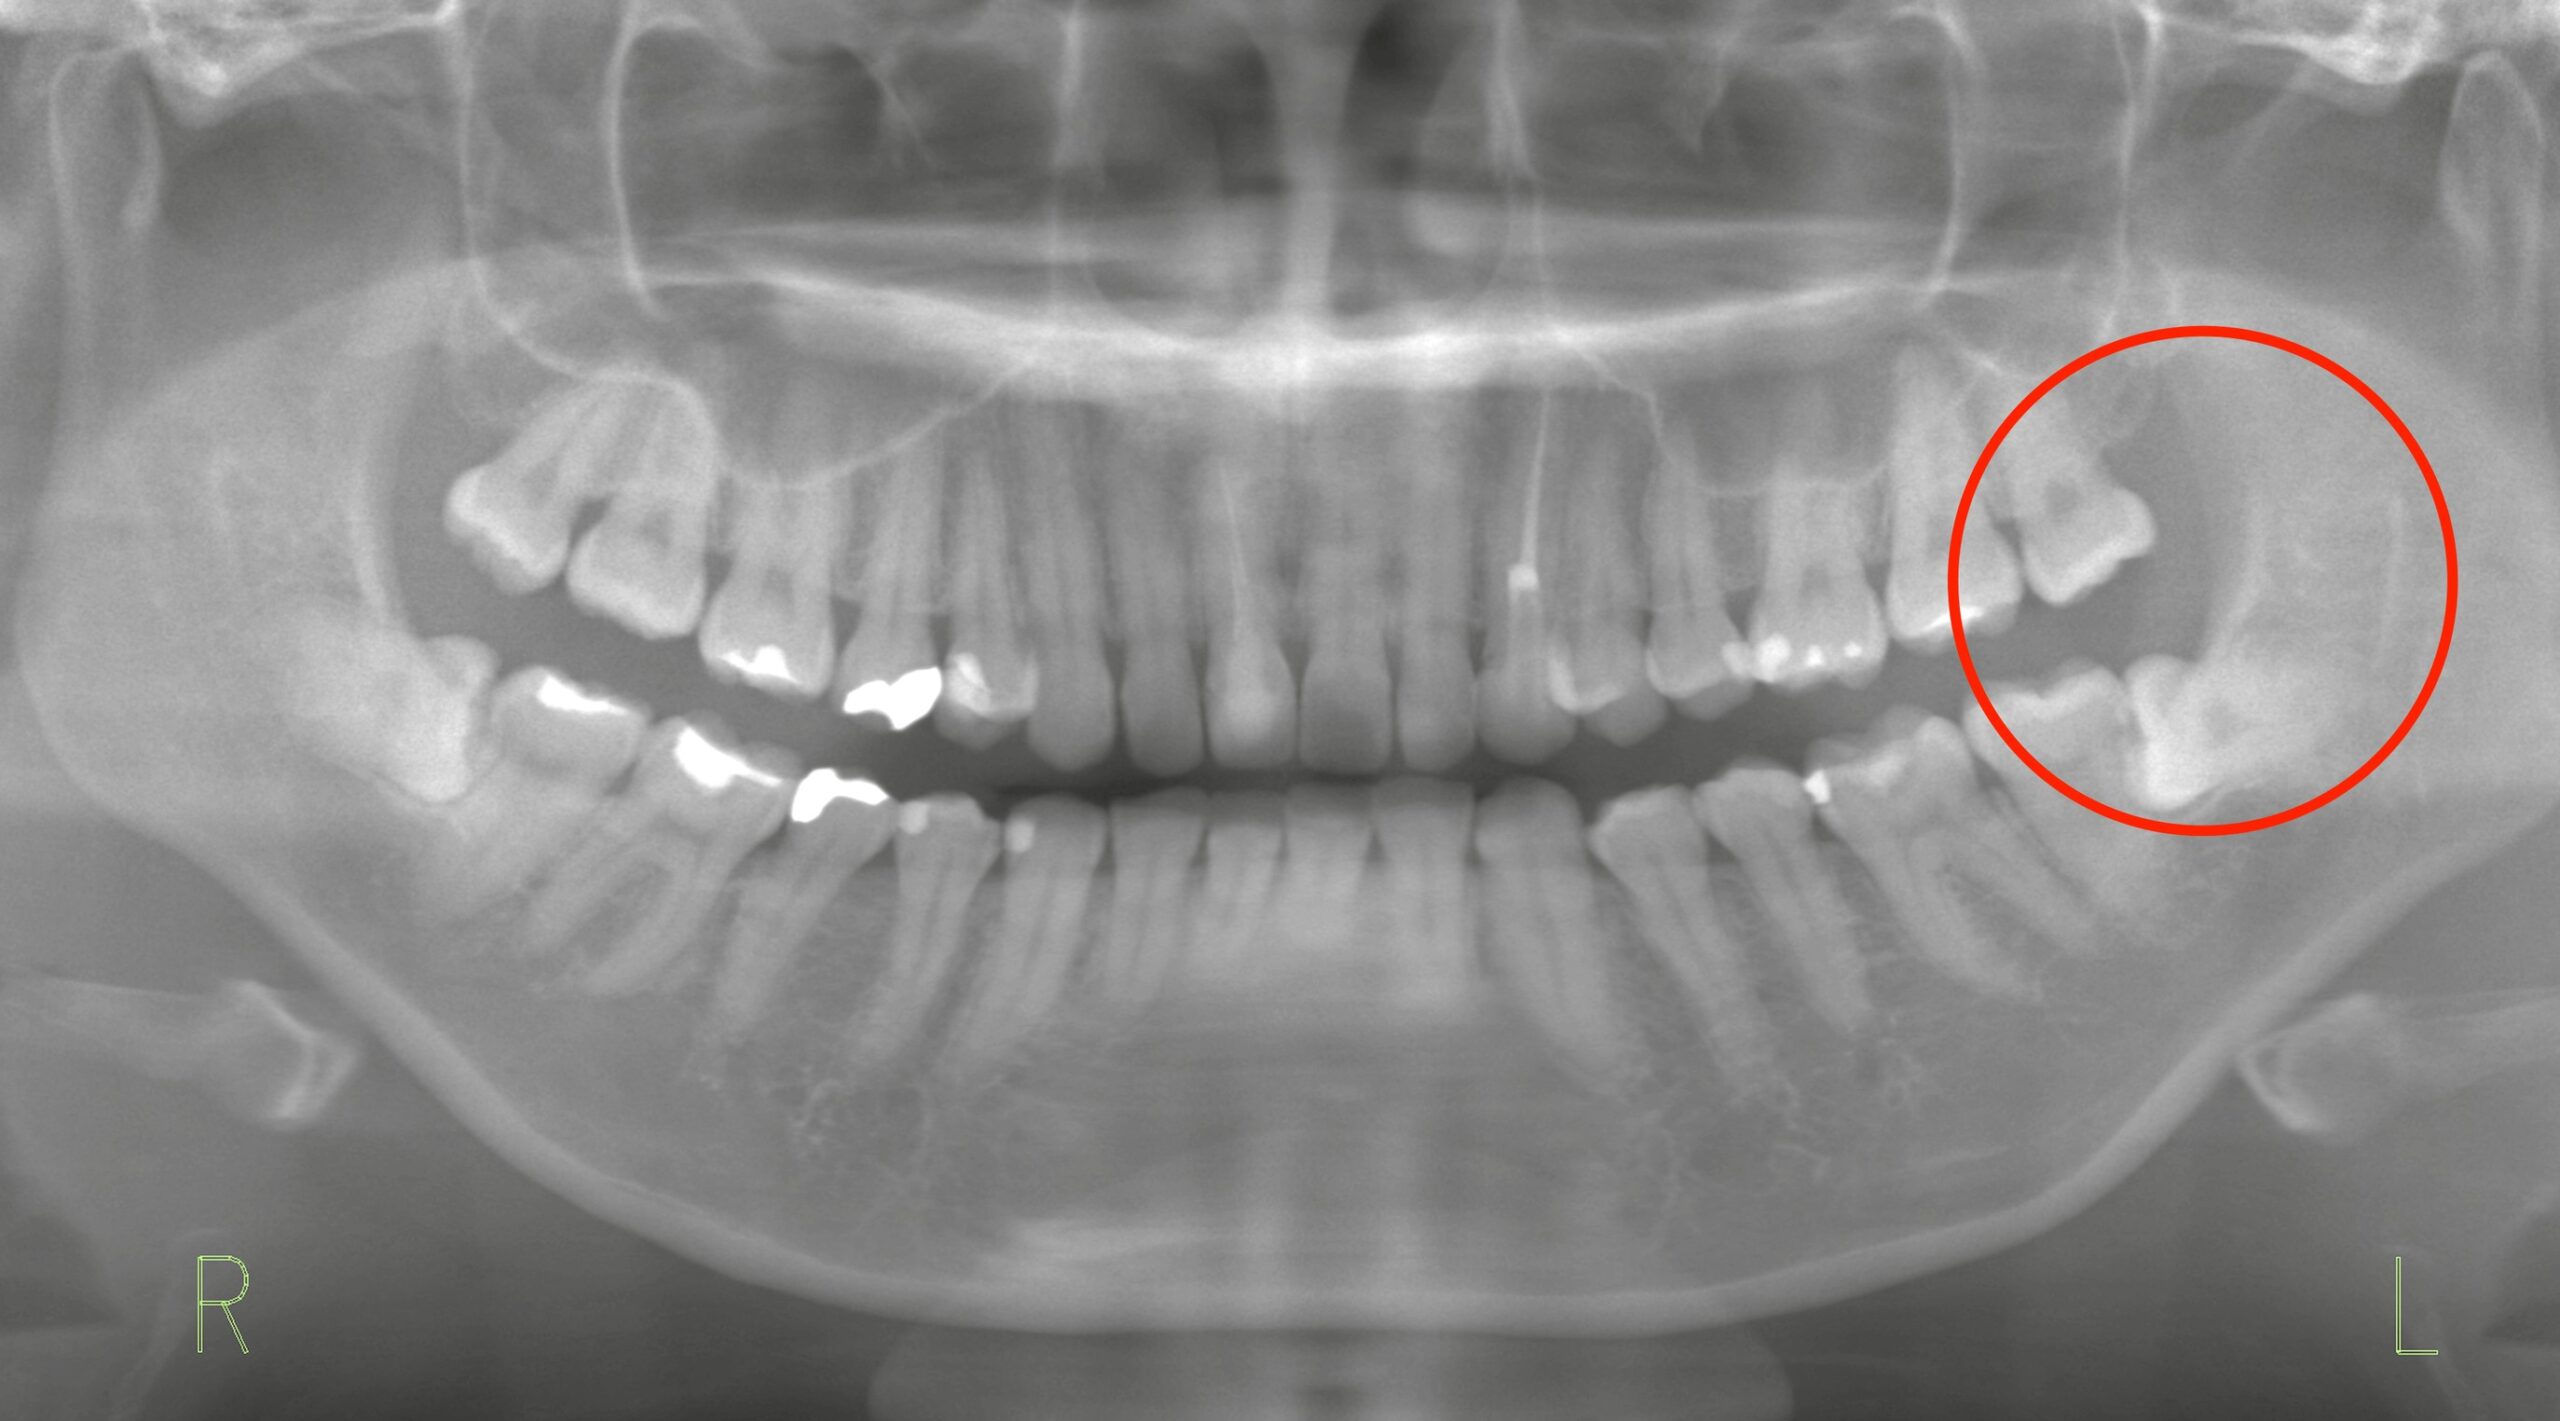

今回ご紹介するのは、左側上下の親知らずの抜歯を希望された患者様のケースです。

下顎の親知らずは埋伏状態で、骨の切削も必要でしたが、術前の計画通りに行えました。